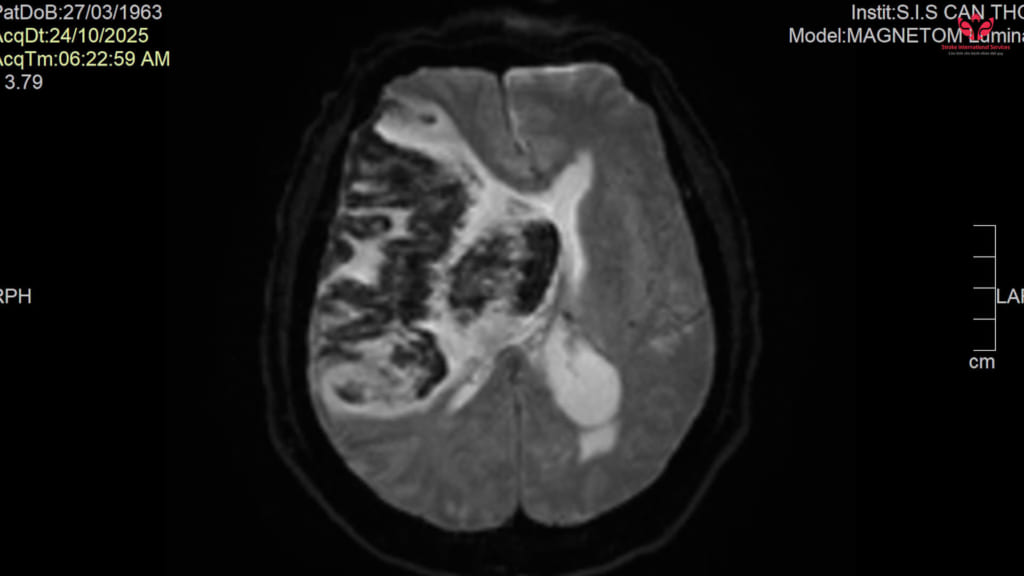

Bệnh nhân N.T.H. (62 tuổi, ngụ phường Khánh Hội, TP.HCM) nhập viện trong tình trạng hôn mê sâu (GCS 4–5 điểm), phải thở máy. Kết quả chụp MRI não cho thấy nhồi máu não diện rộng vùng bán cầu phải chuyển dạng xuất huyết, phù não nặng, kèm nhiều bệnh nền phức tạp như tăng huyết áp, đái tháo đường, rối loạn mỡ máu, bệnh tim thiếu máu cục bộ.